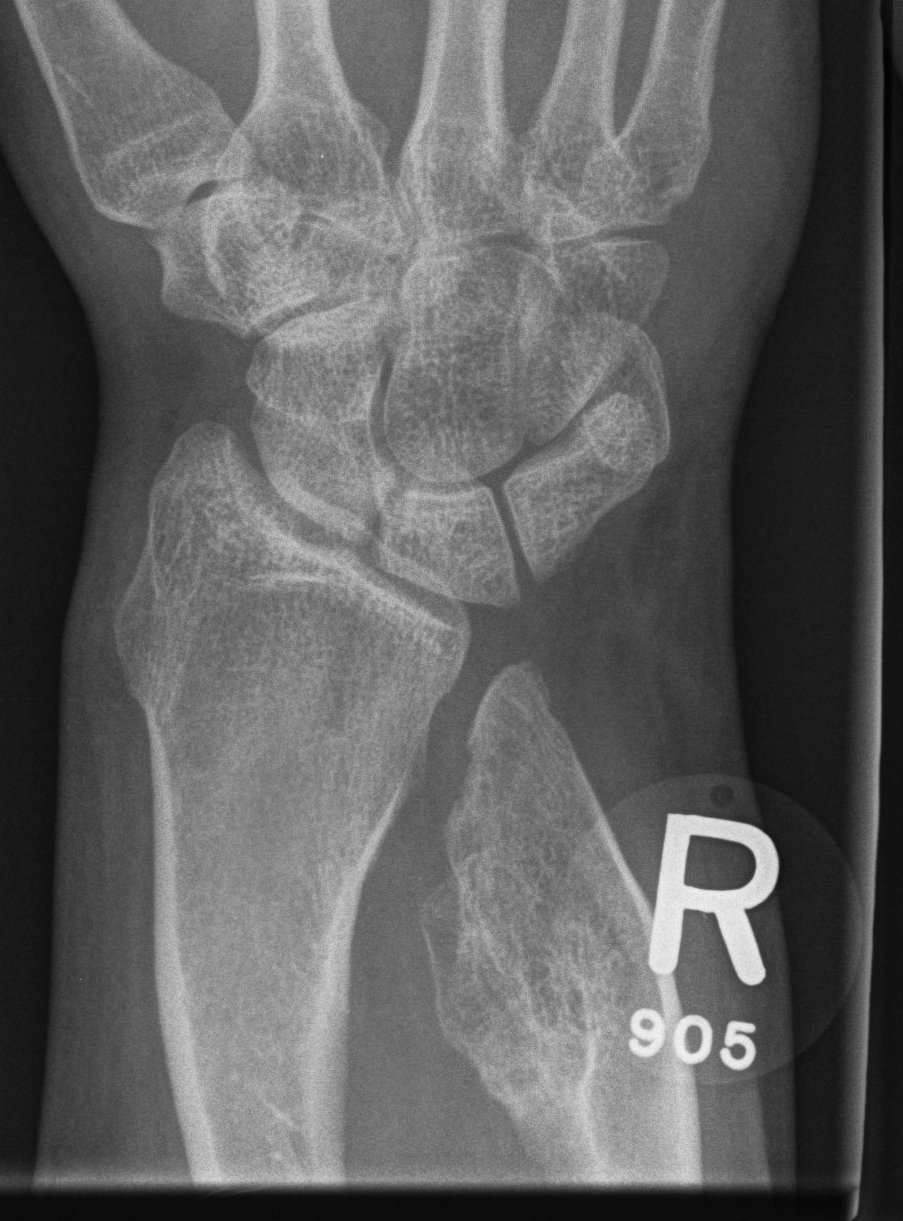

Forearm

- ulnar shortening / radial bowing / ulnar deviation of wrist

- can get radial head dislocation / carpal slip

Osteochondroma ElbowOsteochondromas Forearm 1Osteochondromas Forearm 2

Osteochondromas WristOsteochondromas Wrist LateralMulti OC wrist

Osteochondromas Forearm 1Osteochondromas Forearm 2

Incidence

Jo et al J Hand Surg Am

- 53 pediatric patients with HME

- 10% incidence of radial head dislocation

Issue

Prevent radial head dislocation / radial slip